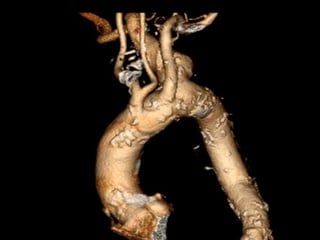

Cas 1

 CTA Pre-opératoire:

 Artere sous clavière aberrante droite

○ Origine a partir de l’aorte thoracique descendante,

distal a l’artere sous-clavier gauche

○ Trajet derriere l’œsophage et la trachée

 Diverticule de Kommerell a l’origine de l’artere

sous-claviere aberrante droite (diamètre 4.6 cm)

 Origine commune des artères carotidiennes

(CCA)

 Artere vertébrale droite dominante qui origine de l

artere sous-clavier aberrante droite

 Aucuns autres anévrismes ou sténoses